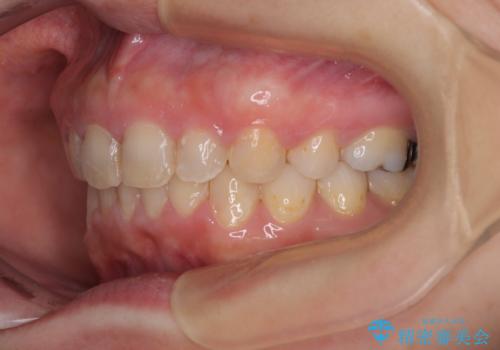

骨格的に上顎が前方にあり、上顎のみの抜歯矯正のため、期間はかかることが予想されましたが、スムーズに移動してくれたおかげで、2年弱の短期間で終えることができました。